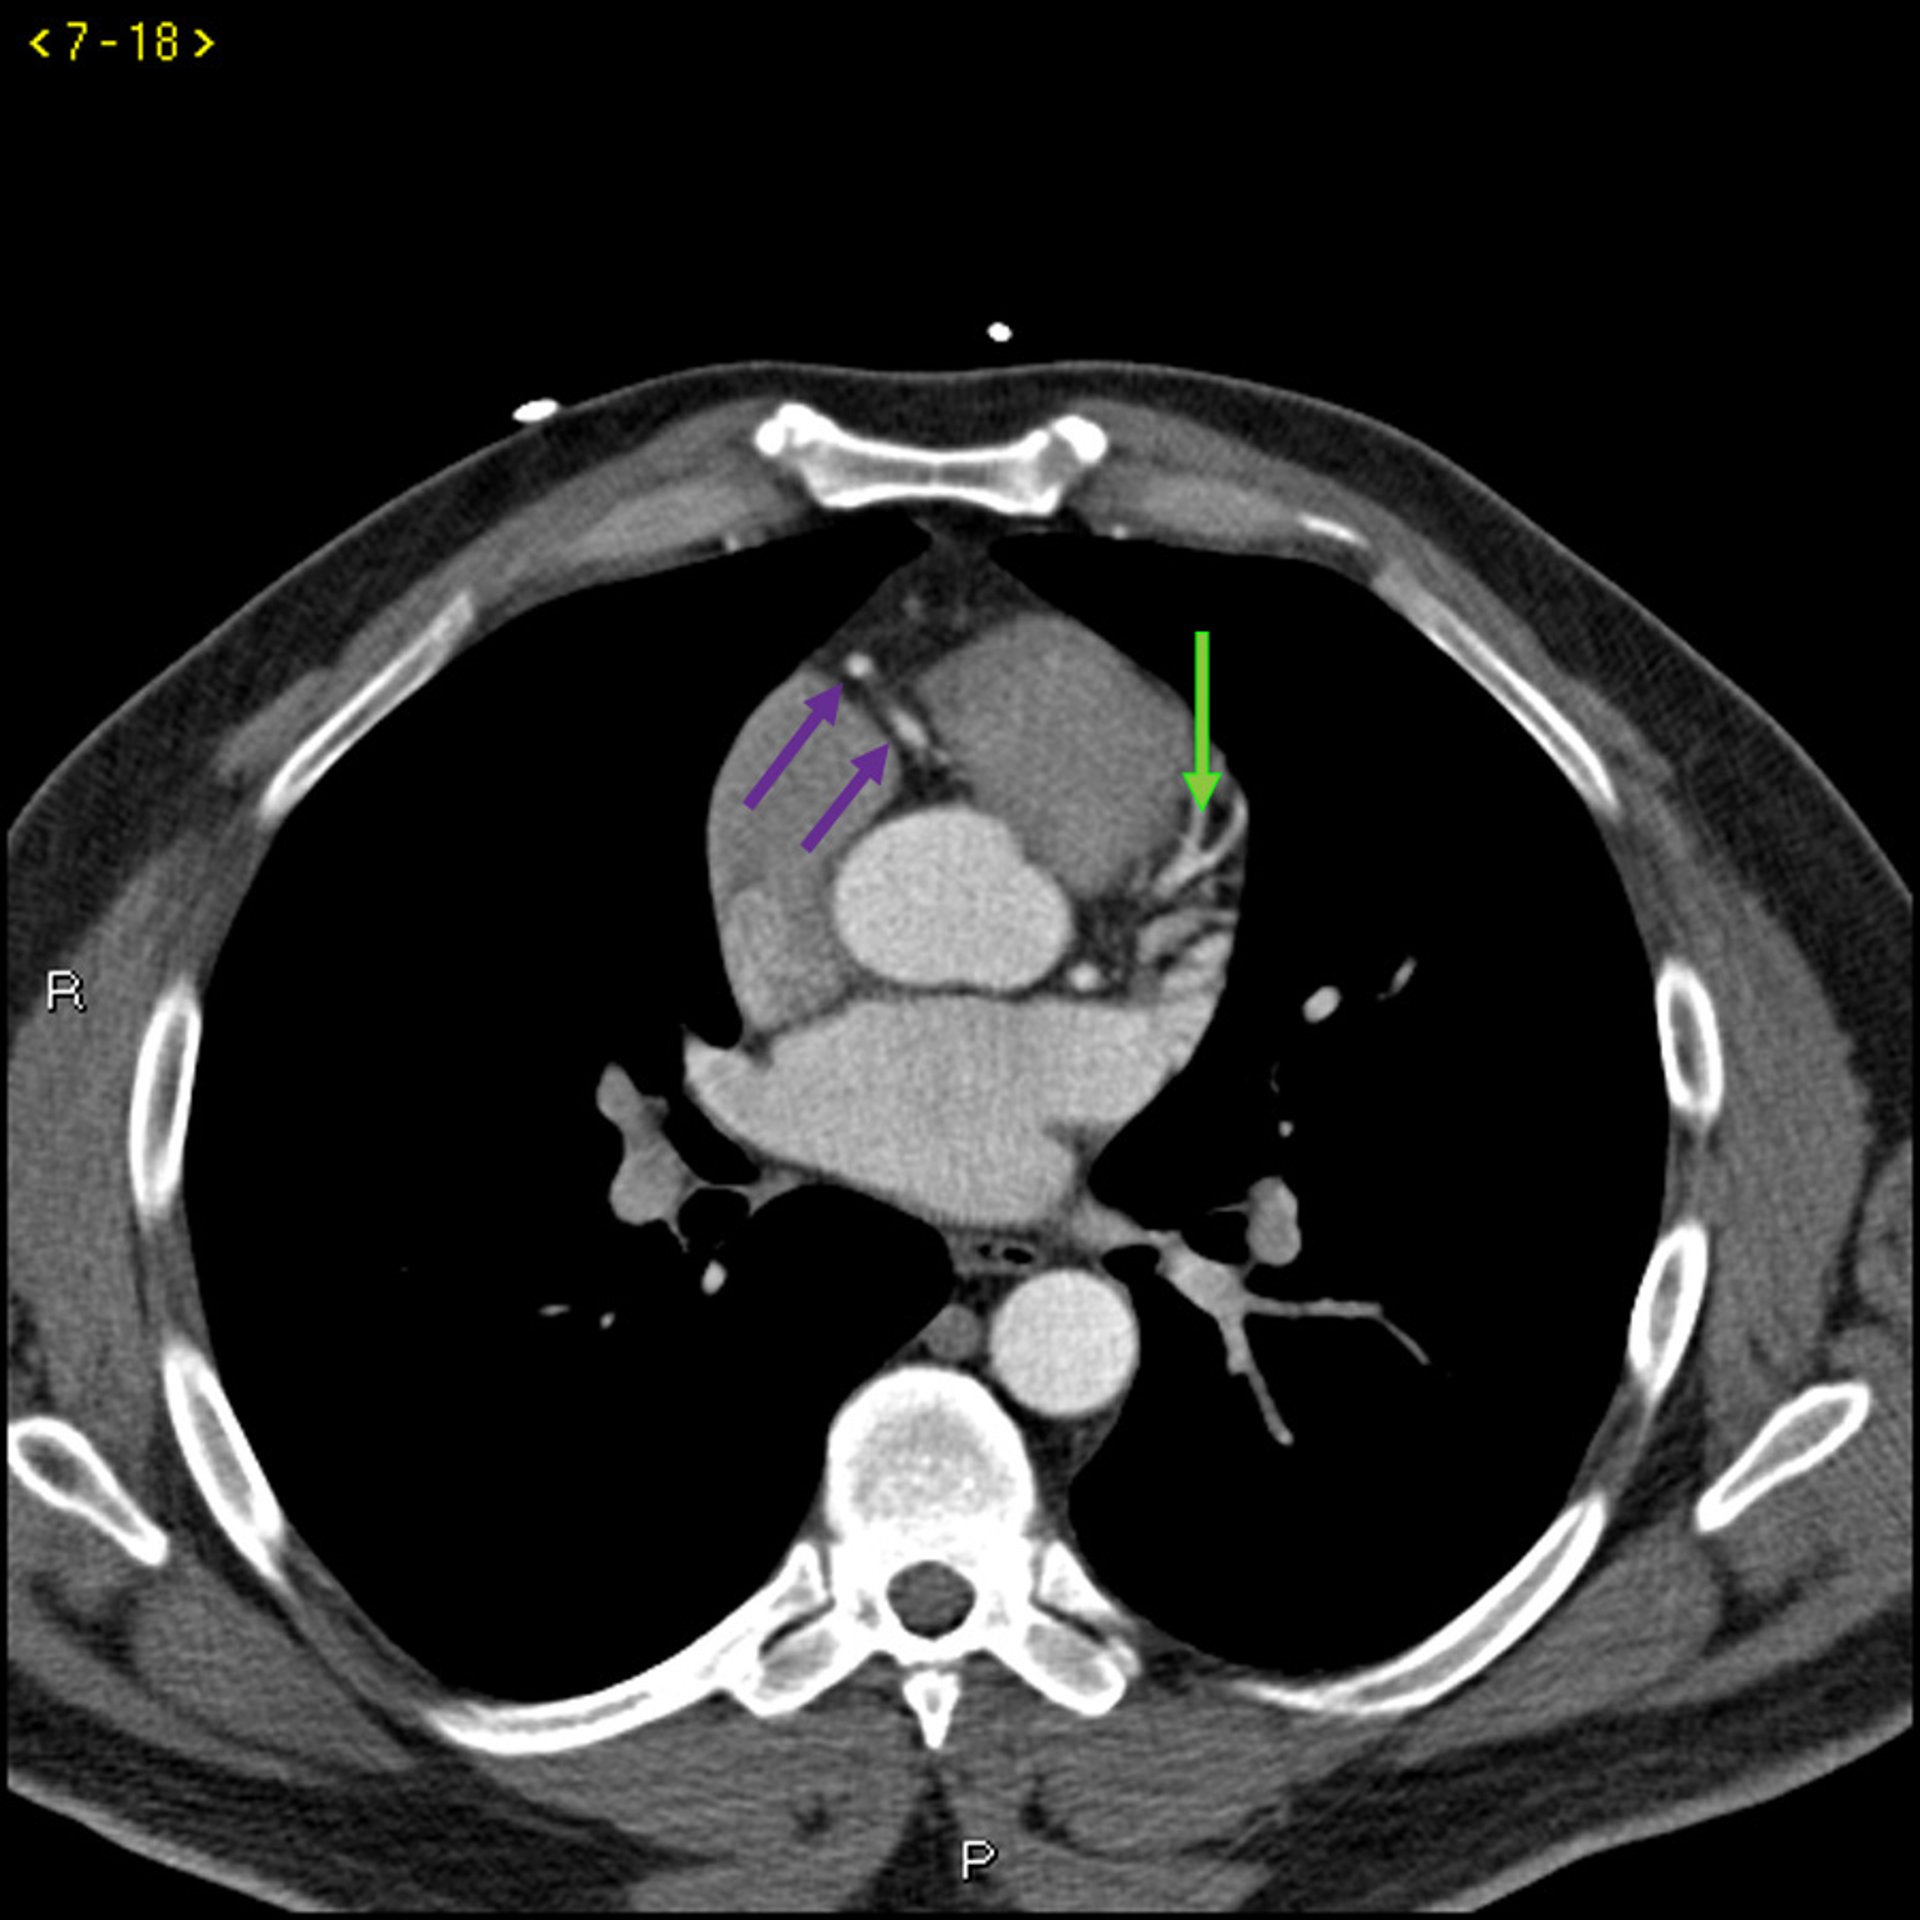

Kontrast CT zeigt normale Koronararterien - Folie 3

Dieses Kontrast-CT zeigt normale Koronararterien. Die linke Hauptleitung ist durch den roten Pfeil gekennzeichnet. Die linke anteriore absteigende Arterie und die linke Zirkumflexarterie sind durch den grünen bzw. blauen Pfeil und die rechte Koronararterie durch den lila Pfeil gekennzeichnet.